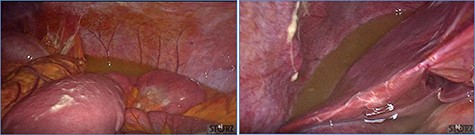

Dilated small bowel loops at laparoscopic exploration: bowel ischemia is evident from the absence of visible vasa recta compared to the adjacent loops (a) 50 cm and (b) 100 cm from the ligament of Treitz.

fluid collection in the peritoneal cavity. Subsequent CT confirmed the presence of diffuse fluid collection in the peritoneal cavity (Fig. 1) but no free air, with distention, bundling and thickening of some small bowel in the left quadrant (Fig. 2). The patient was therefore admitted for supporting therapy (intravenous fluids and antibiotics) with the suspicion of cocaine-induced small bowel ischemia. Twelve hours later, signs and symptoms of diffuse peritonitis developed: worsening diffuse abdominal pain with rebound guarding at examination, a significant increase in WBCs count (16.15 × 103/μl) and neutrophilia (88%), lengthening of coagulation times (INR: 1.68; aPTT: 33.0 s) and increase in fibrinogen (430 mg/dl) and D-Dimer (2275 ng/ml). Therefore, urgent surgical exploration of the abdomen through a three-port open laparoscopic approach was performed, confirming the presence of 1200 ml of exudative fluid and fibrin clots (Fig. 3). Several adhesions between greater omentum, abdominal wall and small bowel underwent blunt dissection. Thorough exploration of the small bowel revealed two ischemic segments located at about 50 and 100 cm from the Treitz ligament (Fig. 4). The large bowel appeared normal. The existence of non-visible gastro-duodenal perforations was ruled out with the administration of 500 ml of saline with 20 ml of methylene blue through the nasogastric tube. An iv bolus of sodium heparin, 10 000 IU, was then administered, performing a 30-min peritoneal lavage with 5 l of saline solution at 37°C. After reaspiration of peritoneal lavage, a new complete exploration of the small bowel was performed, showing complete revascularization of the two ischemic small bowel segments (Fig. 5). Two tubular drainage tubes were placed in the left and right colic gutters. Culture examination of peritoneal exudate was positive for multi-sensitive Escherichia coli and Enterococcus, thus confirming bacterial translocation peritonitis. Postoperative therapy included the administration of iv piperacillin–tazobactam and subcutaneous low molecular weight heparin. Postoperative recovery was smooth, with oral feeding on the second postoperative day (POD), drainage removal on POD 3, complete bowel function restored on POD 4 and home discharge on POD 5. At 15- and 30-day-follow-up, the patient showed full recovery, being now followed by a specialized support structure for his drug abuse.